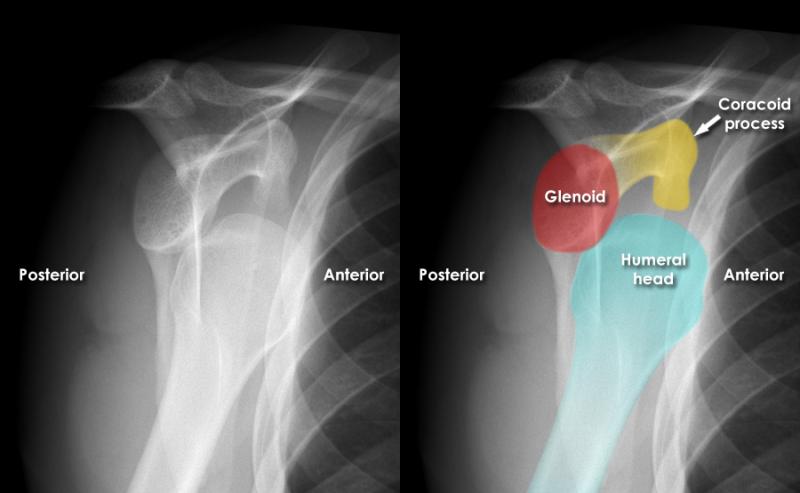

# خلع الكتف وكسر الحديبة الكبيرة: التشخيص والعلاج ## مقدمة حول إصابات الكتف إصابات الكتف شائعة، خاصة بين الرياضيين وا…